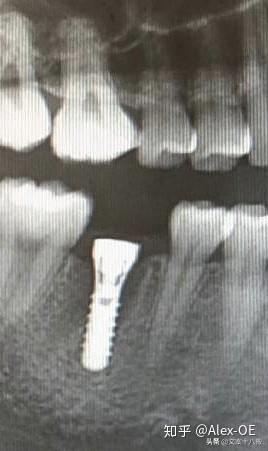

2018年7月6日,下午先拍了CT,很小劑量的輻射。主任方醫(yī)師說我的情況符合植牙條件,骨量也沒有問題,接下來安排了方案并開始手術,由方醫(yī)師操刀,整個手術由3個醫(yī)生共同完成。用消毒水漱口兩分鐘后,躺在那個椅子上,燈光刺眼,消毒棉花在口腔周圍一圈一圈得涂,鼻子上都涂了。身上蓋了做手術的綠布(這個布有名稱嗎?),只露出口腔。因為眼睛也在綠布底下,所以手術全程看不到醫(yī)生用過哪些工具,只能想象醫(yī)生在干什么,做了麻醉感覺不到切開牙齦,鉆孔的疼痛,但是植入牙體是有感覺的,畢竟那么大的東西硬生生的塞了進去,從醫(yī)生手肘的顫動知道這牙題塞進牙槽骨挺費勁的。術前忘記看時間了,估計今天整個過程開始到結束大概40分鐘,40分鐘內(nèi)還包括了十幾分鐘的醫(yī)生的清潔準備工作。沒有什么不適,不過醫(yī)生有一會兒手碰巧壓住鼻子上面的綠布了,就只能用嘴呼吸了。我也沒提醒醫(yī)生覺得很快就過去了,醫(yī)生說有任何不適可以隨時叫停。(因為在清潔的綠布底下,隨意抬手示意會造成污染,能不停就別停了,真的有不適吱聲就行)沒告訴他,大概憋了快一分鐘氣覺得種牙還沒有拔牙痛,只是長時間張著嘴比較難受,術后拍片醫(yī)生說果不錯,配了消炎藥和漱口水,臉貼著冰袋回去了,一周后拆線?,F(xiàn)在已經(jīng)過去8個小時了,麻醉藥也過了,有少量滲血,但疼痛感十分輕微。植牙回去以后,怕麻醉藥過去后疼,下午2點植入后敷冰袋到了晚上8點。那時候確實感覺到疼,不過是輕微而持續(xù)的疼,并且這種輕微的疼大概持續(xù)了四天,術后配的藥也差不多吃完,那之后就沒事了。